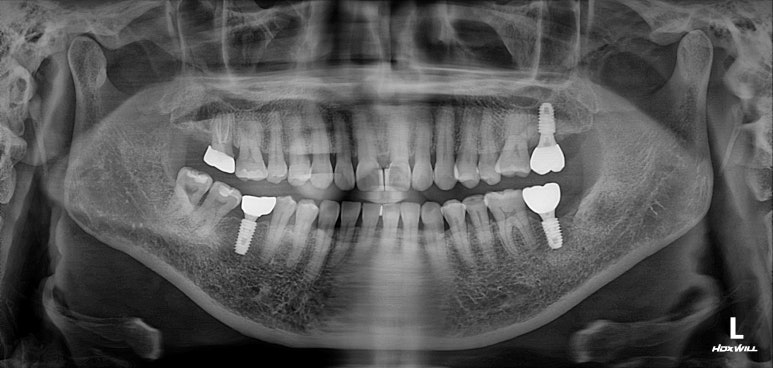

딱 봐도 치아가 조금 없는 것 같으시죠?

빨간색 동그라미로 표시된 곳에 치아가 없어요! 왼쪽 아래 두번째 어금니를 뽑으신 지 몇 년 지나신 상태였습니다.

노란색 동그라미로 표시된 치아는 뿌리만 있는 잔존치근 상태로, 살릴 수 없는 치아였어요.

그리고 마지막으로 파란색 동그라미로 표시된 치아는 기존 크라운 아래로 이차충치가 생겨서 신경치료가 필요한 상태!

제가 여기서 임플란트 치료 잘 되었는지 확인하는 법을 대략적으로 알려드릴께요!

생각보다 이렇게 제작되어 있는 임플란트가 많지 않습니다. 특히 보다 더 비싼 맞춤형 지대주 (custom abutment)를 사용하지 않고 기성 지대주를 사용하면 이렇게 자연스러운 형태가 되기가 힘듭니다.

주변 뼈 높이에 잘 맞게 임플란트가 심겨있어야 합니다. 너무 깊어도 얕아도 좋지 않죠. 노란색 선이 잇몸뼈 높이를 표시한 것입니다.

임플란트 고정체 (fixture) 그리고 나머지의 비율이 1:1이 넘어가지 않는게 좋습니다. 너무 얕은 땅에 긴 전봇대가 심겨있다고 생각해보시면.. 불안하죠 뭔가?

임플란트 크라운의 중간에 임플란트 고정체가 위치해 있는게 이상적입니다. 상황에 따라 달라질 순 있겠지만, 아무래도 임플란트의 뿌리가 머리의 가운데에 있는게 좋겠죠. 츄파춥스 처럼요.

결론은 어쨌든 임플란트가 아~주 이상적으로 잘 제작되었다는 뜻!

임플란트 또한 적절히 유지되고 있고 잘 사용하고 계신 상태입니다.

신경치료와 지르코니아 크라운 치료를 받았던 치아도 뿌리끝 염증 없이 잘 사용중이시구요!